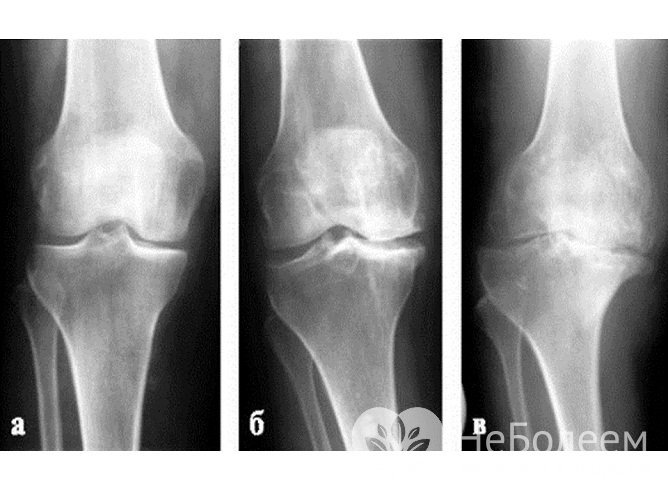

Согласно классификации Келлгрена и Лоуренса (I. Kellgren, I. Lawrence) в зависимости от объективной рентгенологической картины выделяют 4 стадии артроза:

Арторз легкой, средней, тяжелой степени на рентгенографииМедикаментозная терапия: